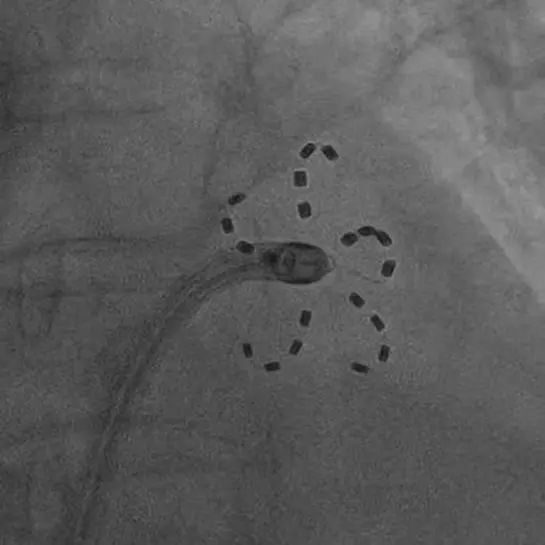

FARADRIVE导管以网篮和花瓣两种形态进行肺静脉消融

与传统的射频消融相比,脉冲消融不需要持续加热心肌组织,从而降低了手术过程中对心脏组织的热损伤风险,极大提高了手术的安全性。将消融导管分别送入四个肺静脉开口实施脉冲电场消融,前后不到20分钟,4个肺静脉的电传导即被彻底阻断,肺静脉电位完全消失。